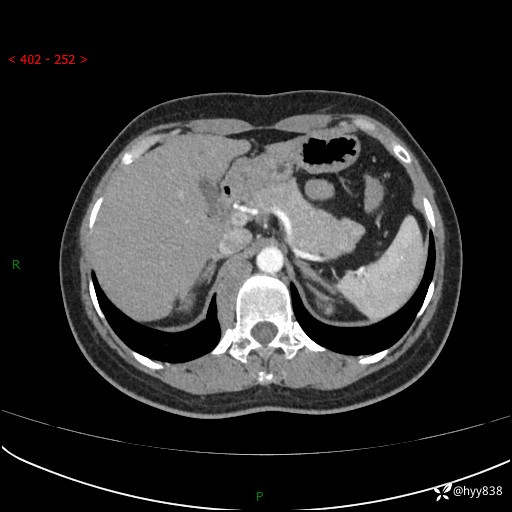

简要病史:患者于1天前因体检发现右旁肾占位,无肉眼血尿,无畏寒发热,无咳嗽咳痰,无腰腹部疼痛不适,无尿频尿急症状,起病来,患者未行特殊治疗,为求进一步诊治,门诊以"右侧腹膜后肿物"收治入院。 发病来患者精神、饮食、睡眠良好,小便如上,大便正常,体重无明显变化。

辅助检查:CT

临床诊断:腹膜后肿物

上腹部CT增强(动脉期+实质期)(外院平扫)